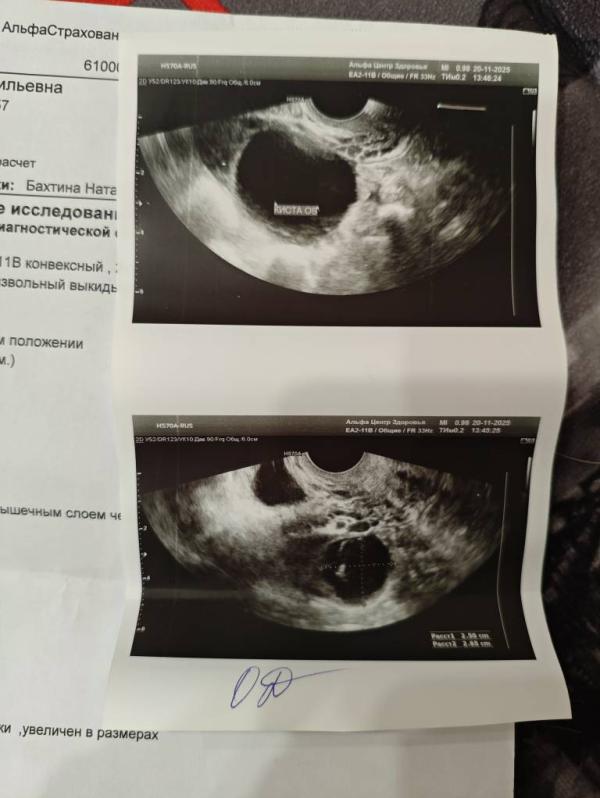

Девочки, подскажите, может кто-то разбирается... Неделю назад была на узи, всё хорошо, был доминантный фолликул, ждала овуляцию, а сегодня в обоих яичниках кисты( овуляции не было, сказала врач

Может это быть кистой жёлтого тела?.. фото прикрепила #первыйпост